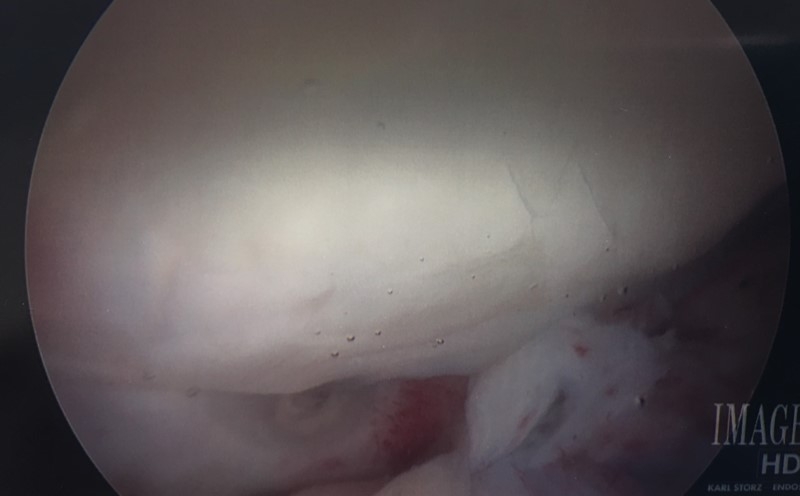

Four months after cartiform to patella